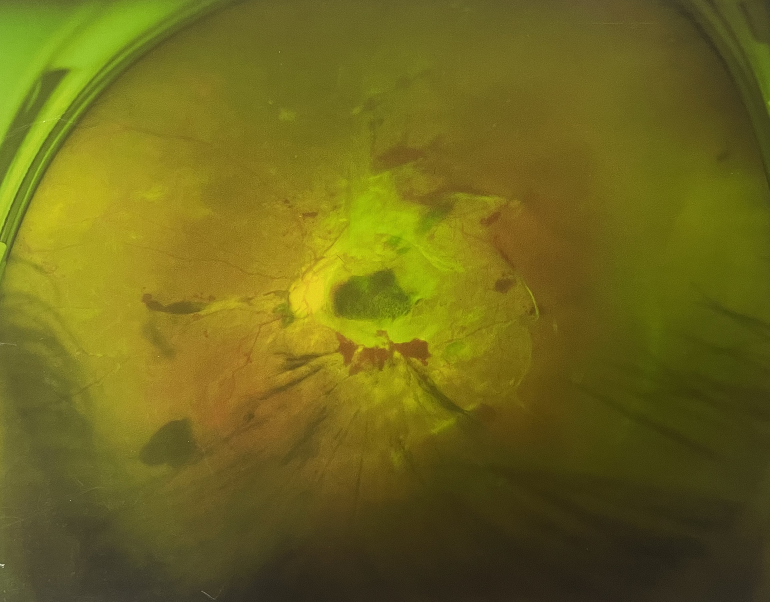

眼底出血一般多久能好?眼底出血可以由眼科本身疾病引起,常見的是視網(wǎng)膜靜脈阻塞、糖尿病視網(wǎng)膜病變、中心性滲出性視網(wǎng)膜病變、視網(wǎng)膜動脈硬化、老年性黃斑病變、視網(wǎng)膜靜脈周圍炎。

另外,眼底出血還可以由全身疾病引起,比如糖尿病可以引起眼底出血,高血壓也會引起眼底出血,還有嚴(yán)重的腎病,血液方面的疾病都可以導(dǎo)致眼底出血。

眼底出血一般多久能好?眼底出血是醫(yī)生用檢眼鏡才能看到,患者和其他人看不見。眼底出血不是單獨的病,一般來說是由眼科本身疾病造成,還可以由全身疾病造成。比如常見的視網(wǎng)膜靜脈阻塞、糖尿病視網(wǎng)膜病變等引起的眼底出血較常見。眼底出血一般多久能好?所以眼底出血的出血吸收時間也不一樣,要根據(jù)病情輕重決定其預(yù)后,出血吸收時間也不一樣。